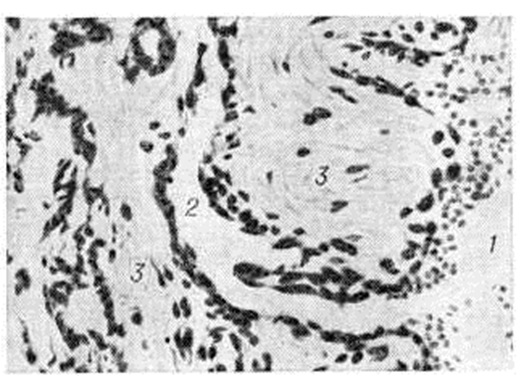

Рис. 3.

Микропрепарат геморроидального узла. Место впадения артерии (1) в кавернозную вену (2). Ход артерии извитой (3). Окраска пикрофуксин-фукселином; × 280.

Кавернозные вены прямой кишки при Геморой постепенно увеличиваются, принимают вид покрытого слизистой оболочкой узла на широкой ножке, свисают в просвет кишки и могут выпадать из анального отверстия. Стенки таких узлов истончены, нередко изъязвлены или аррозированы. При микроскопическом исследовании удалённых геморроидальных узлов обнаруживается гиперплазия кавернозных телец [Штельцнер (F. Stelzner), 1963]. Стенки кавернозных вен утолщены, склерозированы, число артериовенозных анастомозов в них возрастает, просвет их расширяется (рисунок 1—3).